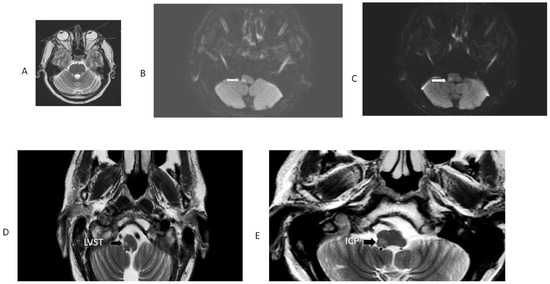

| 1 R OLD 52 | RE: 32.2 LE: 32.2 Hypometric saccades | R lateral medulla, cerebellar tonsil, uvula, and nodulus. | H direction changing | Normal | No | Noted at 32 h exam; present 6 weeks later. Resolved between 6 weeks and 5 months | Ataxia grade 3 to right |

| 2 R OLD 75 | RE: 21.9; LE 22.4. Hypometric saccades | R lateral medulla and lateral cerebellum. | H second degree to L | Normal | Ocular tilt reaction | Noted at 30 h exam; present during hospital stay for 3 days. | Ataxia grade 3 to right |

| 3 L OLD 88 | RE: 22.4; LE 26.6 Single rapid corrective saccades | L lateral pons, mid basilar stenosis. | H second-degree L | Abnormal | No | Noted at 24 h exam. Present for 5 days in ICU until cardiac arrest. | Ataxia grade 2 to left |

| 4. L OLD 61 | RE: 25.9; LE:30.3 Hypometric saccades | L lateral medulla. | H second-degree R | Normal | Yes | Noted at 72 h exam. | Ataxia grade 3 to left |

| 5. R OLD 41 | RE: 34.9; LE 25 Hypometric saccades | False-negative in initial MRI. Second MRI: stroke R lateral medulla. | Primary gaze h LBN. Did not follow Alexander’s Law | Normal | Yes | Noted at first exam and at 12 h. Resolved in 48 h. | Ataxia grade 3 to right |

| 6. L OLD 49 F | RE: 21.4; LE: 36.2 Hypometric saccades | False-negative in initial MRI. Second MRI: L lateral medulla. | H 1st-degree RBN | Normal | Yes | Not checked at first visit; present at 36 h exam; lost to f/u. | Ataxia grade 2 to left |

| 7. R OLD 62 F | RE: 13.6; L:0.1 Hypometric Saccade | False-negative in initial MRI. Second MRI: stroke R lateral medulla. | H LBN second degree | Normal | yes | OL Noted at 24 h exam, resolved in 12 h. | Ataxia grade 3 to right |

| 8 R OLD 63 M | RE: 29.3; LE: 27.35 | R lateral medulla. | Second-degree torsional to L shoulder/h-RBN | Normal | OTR | Noted at 32 h exam. | Ataxia grade 3 to right |

| 9 R OLD 51 M | RE: 35.6; LE 26.6 | False-negative in initial MRI. Second MRI: stroke R lateral medulla. | UBN | Normal | yes | Noted at 48 h exam. | Ataxia grade 3 to right |

| 10 R OLD 59 M | RE: 45.3, LE: 42.3 | R dorsolateral medulla. | Bilateral h gaze-evoked nystagmus | Normal | Yes | OLD at 6 h | Ataxia grade 2 to right |

| 11 R OLD 28 M | RE: 35.6, LE: 20.9 | R lateral medulla and cerebellum. | H LBN torsional top pole to left shoulder. | Normal | No | OLD at 24 h. | Ataxia grade 3 to right |

| 12 L OLD 39 M | RE: 22.4, L: 18/1 | L lateral medulla and cerebellum. | H RBN in center fixation, h-gaze-evoked nystagmus. | Normal | No | OLD at 24 h. | Ataxia grade 3 to left |

| 13. R OLD 45 M | RE:40, LE: 34.4 | R lateral medulla. | No nystagmus. | Normal | No | OLD at 6 h. | Ataxia grade 3 to right |